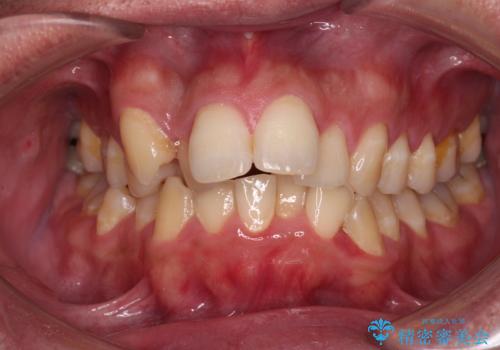

- デコボコと前歯の突出感を気にして来院された患者様です。

舌の突出癖などにより上顎前歯が前方に突出し、さらに歯列幅が狭小になっている状態でした。

また、上顎歯列全体が下顎に対して前方位に位置していました。